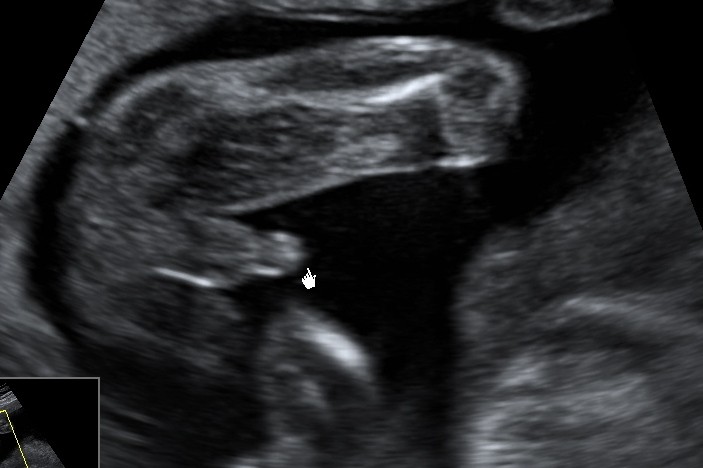

We wtorek mam badanie połówkowe, mój mąż nie może się doczekać bo pierwszy raz moze wejść na badanie że mną :)